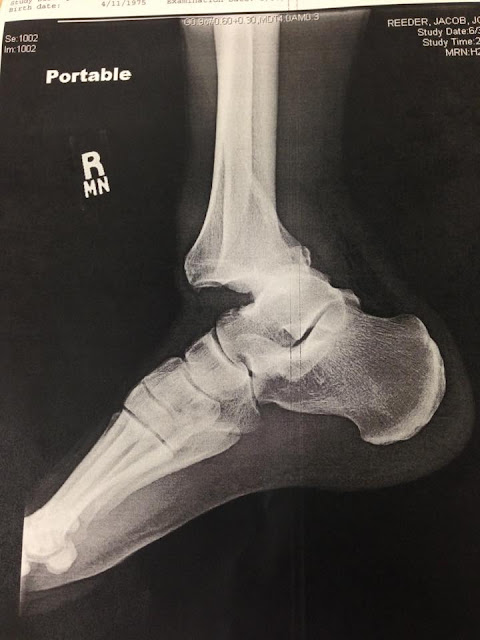

This was the before photo. The leg bone is not exactly connected to the foot bone. It was all screwed up.

Now it's all screwed together.

ReplyDeleteAs an ex-x-ray technician, I can say that it looks like he has good strong bones. That's a pretty impressive metal brace sewn into his leg. Amazing what they can do. Just looking at the before picture gives me pain. Glad he is all patched up!